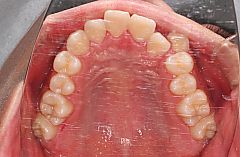

主訴は前歯の凸凹(叢生)が気になるとのことでした。特徴的なのは上顎左側の八重歯です。八重歯のことを専門用語では犬歯の低位唇側転位といいます。上の方にあるのになぜ「低位」なのかといいますと、歯科では上下顎の歯が咬む面を最も高い位置であるとみなすからです。ですから咬む面から遠ざかるなら上でも下でも低位となります。地面を基準に考えるのが普通ですからややこしいですね。

上下顎の多数歯に渡り歯頸部に白濁が認められます。これは虫歯になる初期段階です。これが進行して実質欠損を生じるようになると治療が必要ですから、フッ素塗布など、歯質強化を図りながら注意深く経過観察することにしました。

この症例では歯をきれいに配列するためのスペースが上顎で8mm、下顎で6mm不足しています。矯正治療で歯を配列するためのスペースを確保する方法は大きく2通りあって、一つは抜歯、もう一つは歯列の拡大です。日本人の場合、欧米人と比べると鼻が低くオトガイも突出していないことが多いので、歯列の拡大でスペースを確保すると相対的に口元の突出感が悪化してしまうことが多いので抜歯によってスペースの確保をおこなうことが多くなります。この症例でも上下顎両側の第一小臼歯を抜歯することとしました。